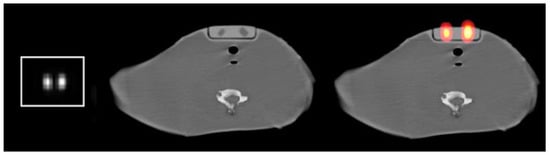

2.1. Method for Calculating Small Sizes of Volumes

2.1.1. Concept

2.1.2. MATLAB Calculations